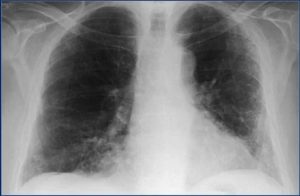

Флюорография — это исследование грудной клетки посредством облучения рентгеновскими лучами, с фиксированием результатов исследования на пленку. Методика уже несколько устаревшая, но все еще являющаяся наиболее дешевым способом проверить свои легкие на предмет наличия каких-либо патологий.

Принцип получения результатов

Врач-рентгенолог визуально отличает на фотопленке изменения в плотности тканей легких. Те места, где плотность выше, чем у здоровых легких, свидетельствуют о каких-то проблемах в тканях. Соединительная ткань, разрастаясь, замещает легочную ткань и на флюорографии выглядит более светлыми участками.

Многое в результатах зависит от квалификации и опыта врача. Был даже такой курьезный случай, когда молодой врач увидел затенение в левой половине легких, стал бить тревогу, а оказалось, что это сердце! Но, это, конечно, из разряда врачебных легенд.

Что можно увидеть на снимках

Различают спайки, фиброзы, наслоения, тени, склерозы, тяжистости, лучистости, рубцовые изменения. Все эти аномалии, если они присутствуют, видны на снимках легких.

Если человек болен астмой, то на снимке будет видно, что стенки бронхов у него утолщены, это связано с тем, что на них приходится более высокая нагрузка. Также на снимках можно идентифицировать кисту, абсцессы и каверны, кальцинаты, эмфиземы, рак.